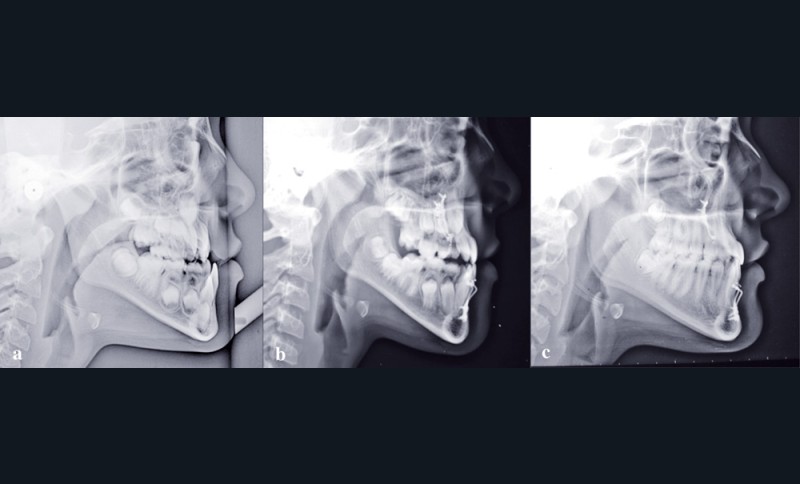

Si l’on analyse le résultat du point de vue squelettique, on constate une belle amélioration orthopédique du prémaxillaire, stable dans le temps. La croissance maxillaire a heureusement été toujours supérieure à la forte croissance mandibulaire. On note après orthopédie un bon support osseux pour la lèvre supérieure qui présente une meilleure épaisseur. À la fin de la croissance, les courbures naso-labiale et labio-mentonnière sont optimisées (fig. 5).

Les téléradiographies de profil confirment la croissance du maxillaire avec une légère tendance rotationnelle antérieure et une avancée du point A de 8 mm. La croissance mandibulaire est homothétique sauf dans la région du point B où elle est freinée (fig. 6-7).